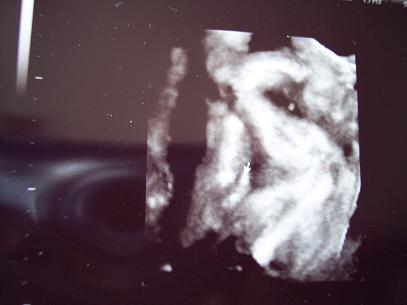

Ma megyek 4D re ,kivi vagyok mekkorára növesztettem a kicsifiam.Ha kicsifiú egyáltalán :wink: :lol:

Mert mostanság mindenki azt mondja ez tuti kiscsaj ,semmi hasad nincs.

Kicsit már rosszul érzem magam emiatt,de nem értik én nagydarab vagyok azért nincs akkora hasa mint egy kis filigrán nőcinek.

Képek

Képkukink

Kép pofikánk

Kép ismét